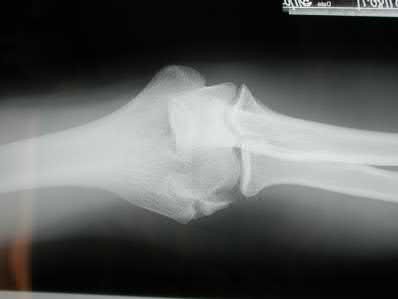

Figure A is an AP radiograph of a posterior knee dislocation. Figure B is a lateral showing the same injury.